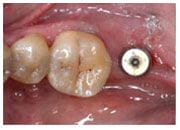

植牙過程

植入植體

治療後